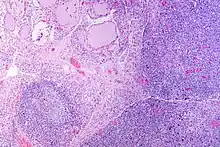

The thyroid of someone with Hashimoto's thyroiditis as seen with a microscope at low magnification

High powered magnification showing lymphocytic infiltration of the thyroid gland in autoimmune thyroiditis

Marked lympocytic infiltration (purple areas) of the thyroid gland in a patient with chronic autoimmune thyroiditis

Gross pathology of a thyroid with autoimmune thyroiditis may show an symmetrically enlarged thyroid.[22] It is often paler in color, in comparison to normal thyroid tissue which is reddish-brown.[22] Microscopic examination will show infiltration of lymphocytes and plasma cells. The lymphocytes are predominately T-lymphocytes with a representation of both CD4 positive and CD8 positive cells.[22] The plasma cells are polyclonal, with present germinal centers resembling the structure of a lymph node.[22] Fibrous tissue may be found throughout the affected thyroid as well.[22] Generally, pathological findings of the thyroid are related to the amount of existing thyroid function - the more infiltration and fibrosis, the less likely a patient will have normal thyroid function.[22] In late stages of the disease, the thyroid may be atrophic.[12]

Histologically, the hypersensitivity is seen as diffuse parenchymal infiltration by lymphocytes, particularly plasma B-cells, which can often be seen as secondary lymphoid follicles (germinal centers, not to be confused with the normally present colloid-filled follicles that constitute the thyroid). Atrophy of the colloid bodies is lined by Hürthle cells, cells with intensely eosinophilic, granular cytoplasm, a metaplasia from the normal cuboidal cells that constitute the lining of the thyroid follicles. Severe thyroid atrophy presents often with denser fibrotic bands of collagen that remains within the confines of the thyroid capsule.[52]